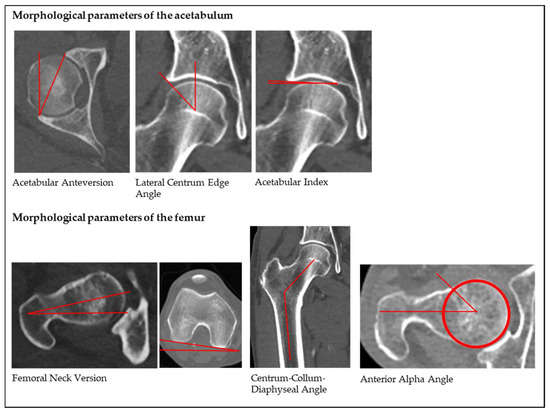

2.2. Radiological Assessment and Parameters

3.1.1. Acetabular Anteversion (AcetAV)

3.1.2. Lateral Centrum Edge Angle (LCE)

3.1.3. Acetabular Index (AI)

3.1.4. Femoral Neck Version (FNV)

3.1.5. Centrum-Collum-Diaphyseal Angle (CCD)

3.1.6. Anterior Alpha Angle (AαA)